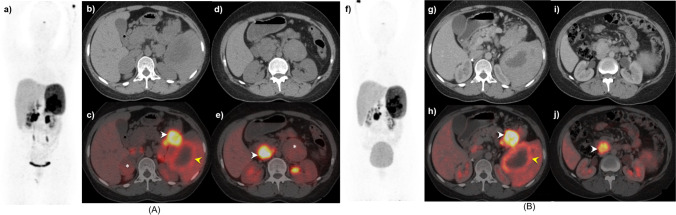

Figures 3, 4, and 5 A and B show the 68 Ga-DOTANOC PET/CT images of patients referred for initial diagnosis; for the evaluation of post-surgery disease status; and for both initial diagnosis and post-treatment disease status of VHL, respectively.

A 21-year-old female, with known VHL, underwent 68 Ga-DOTANOC A at baseline (MIP: a) and B post-operative follow-up (MIP: f). At baseline, CT and fused PET/CT axial images (b, c) reveal a hypodense right supra-renal lesion with mild tracer uptake (asterisk), intensely tracer avid hypodensity in the tail of the pancreas (white arrowhead), and an adjacent heterogeneous splenic lesion with peripheral tracer uptake (yellow arrowhead). Other.68 Ga-DOTANOC avid lesions seen in the lower sections in CT and fused PET/CT images (d, e) involving the left adrenal (asterisk) and an intensely avid precaval mass at the level of L2 vertebra (white arrowhead), suggestive of paraganglioma. Post bilateral adrenalectomy, follow-up axial CT and PET/CT images (g, h and i, j) revealed no residual disease in bilateral supra-renal regions with no significant interval change in the paraganglioma, pancreatic, and splenic lesions compared to baseline (stable disease)